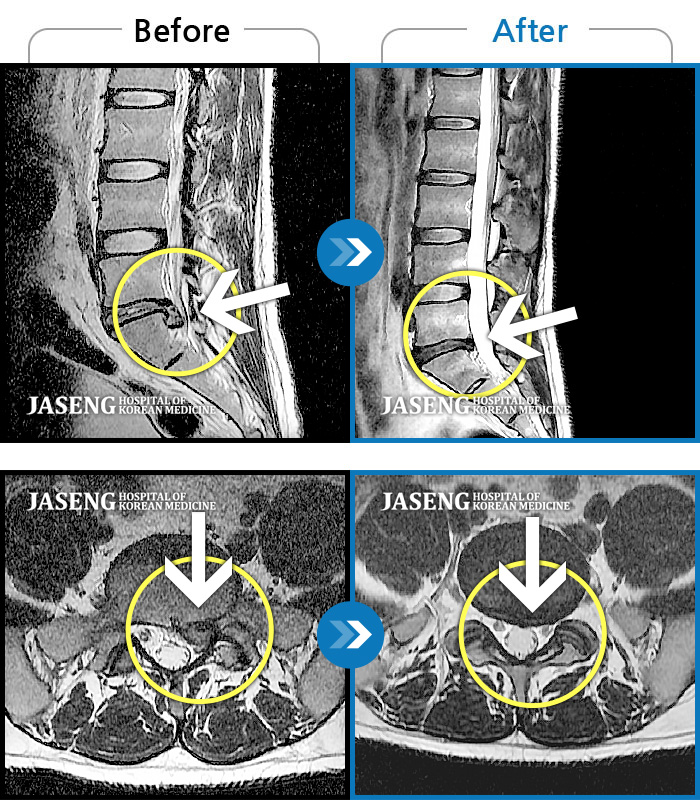

ȯںп  Ǹ   ǿ ԿǾ, ο  ġ  ۿ     Ƿ   ġḦ Ͻñ ٶϴ.